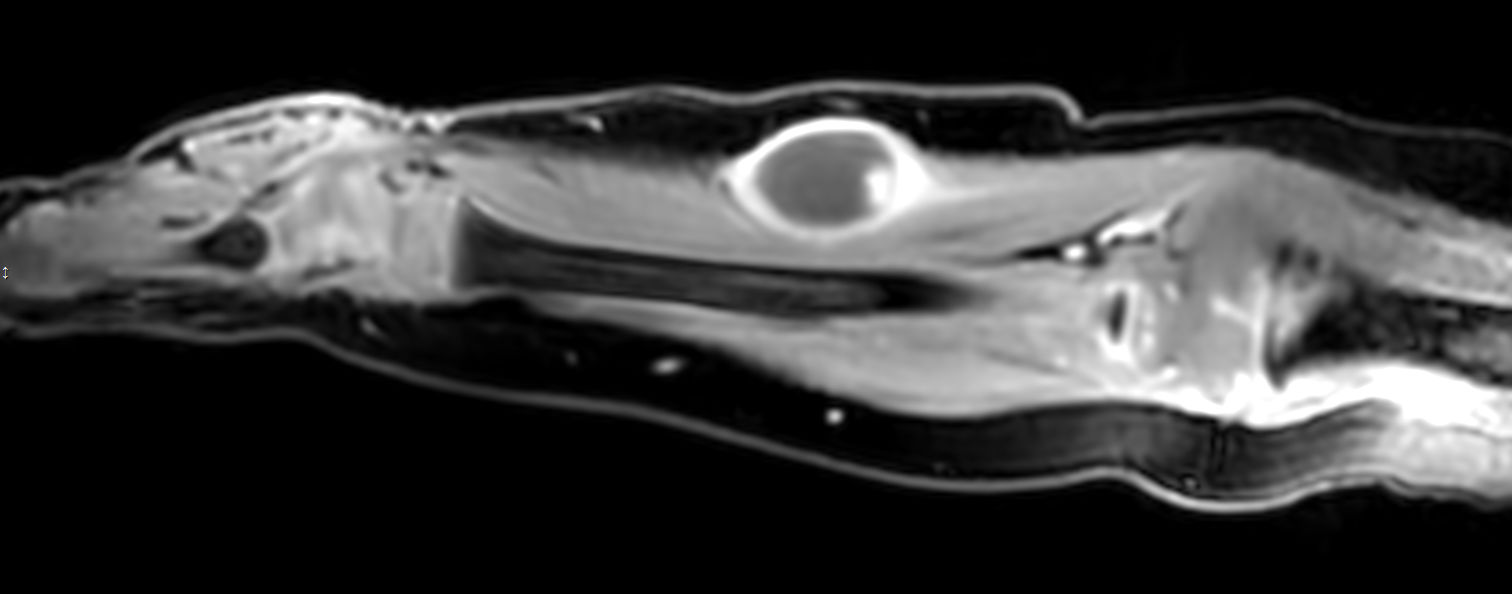

Pediatric patient with a lesion in the forearm. mDIXON XD provides uniform fat-free imaging and allows for multiple image types in one single scan. Integration of Compressed SENSE acceleration technique enables speeding up of the entire exam.

Coronal T2w mDIXON XD (Water only)Compressed SENSE